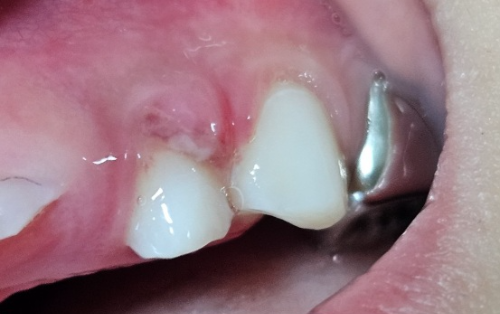

아이와 함께 지하철에서 내려서 계단을 올라가고 있는데 아들이 먼저 가겠다고 뛰다가 미끄러졌습니다. 신나게 말하며 빨리 올라가다가 입을 벌린 상태로 계단 턱에 치아를 부딪혔습니다. 입 가리며 통증을 호소했는데 치아를 보니 잇몸에서 피가 많이 흐르고 윗니의 앞니 주변 잇몸색이 변했다가 다시 돌아오는 듯했습니다.

앞니는 영구치여서 뿌리에 이상이 있을 수도 있고 앞니 옆니에 피가 많이 나서 치과에 가보기로 했습니다. 겨우 달래어서 치과에 가서 사고에 대해 이야기한 후 진료를 받았습니다. 치아 상태를 확인하기 위해 부분 엑스레이 촬영을 했습니다.

- 다행스럽게 영구치 앞니의 뿌리에 손상은 없음. (앞니는 부딪히지 않았을 수도 있는 것 같아요. 하지만 혹시 모르니 치아 컬러가 변해 멍니가 되면 치과에 다시 내원해서 확인이 필요함.)

- 피가 많이 나는 치아는 유치임. 유치 뿌리 한쪽이 없어진 상태로 보여서 나중에 불편함이 있으면 발치를 하면 된다고 함. 피가 많이 나는 것은 잇몸에 상처도 많이 나고 치아가 부딪히면서 쉽게 말하면 '인대가 늘어났다'라고 생각하면 된다고 함. 그래서 며칠간은 가급적 앞니로 음식물을 씹지 않도록 주의하면 빨리 나아질 것이라고 함.